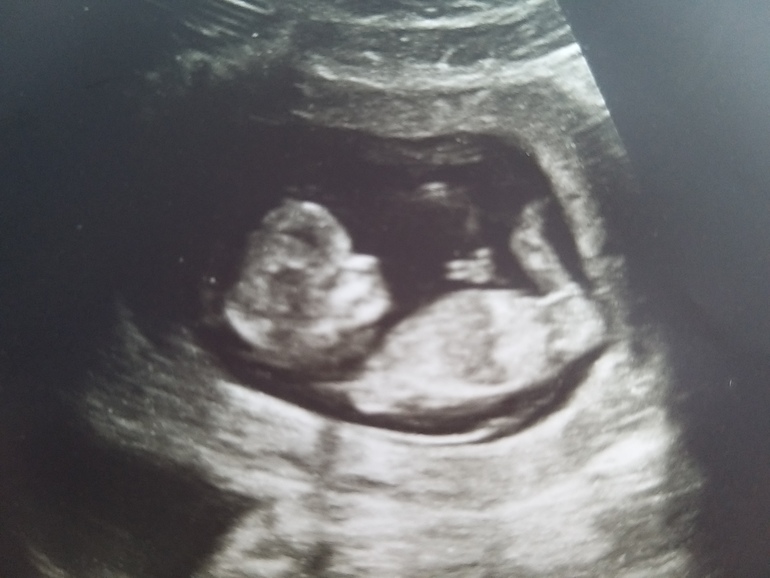

Скрининг 12+2

Целый месяц не была на узи 😱 Так переживала, что будут плохие новости)

Но нет, всё замечательно, отклонений нет по узи.

Пол не предположили, но надежду на девочку еще сохраняю)